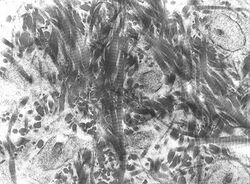

| File:Bertazzo S - SEM deproteined bone - wistar rat - x10k.tif A scanning electronic micrograph of bone at 10,000× magnification | |